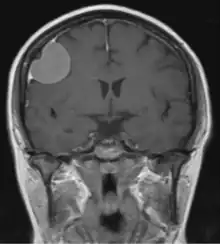

The dural tail sign (also known as "dural thickening", "flare sign", or "meningeal sign") is a radiological finding observed in magnetic resonance imaging (MRI) studies of the brain that refers to a thickening of the dura mater immediately adjacent to a mass lesion, such as a brain tumor.[1] Initially, the dural tail sign was thought to be pathognomonic of meningioma, a slow-growing tumor that arises from the meninges.[1] However, subsequent studies have shown that it can also be observed in various intra- and extra-cranial pathologies and in spinal lesions.[1] It is not a completely sensitive finding, as it is seen in only 60-72% of cases.[2] It is not completely specific either, as it has been described associated with lesions like neuromas, chloromas, pituitary diseases, granulomatous disorders, cerebral Erdheim-Chester disease, lymphomas, metastasis, hemangiopericytomas, schwannomas, and gliomas such as glioblastoma multiforme (GBM).[2][3] The final diagnosis should be further established through cerebrospinal fluid analysis or histopathological examination following a biopsy.[3]